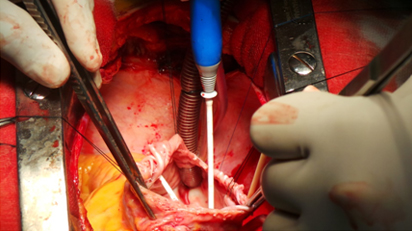

Surgical ablation (also referred to as a modified Maze procedure or Mini Maze procedure) involves the use of radiofrequency waves (modified electrical energy) to create precise scar lines on the heart's surface. These scars redirect the erratic electrical impulses of atrial fibrillation to a normal electrical pathway through the heart. Heart surgeries, such as mitral valve replacements along with Tricuspid valve repair are procedure which are performed in patients with atrial fibrillation.

Cardioblate System

Cardioblate System

Application of Abalation around Pulmonary Veins

Cardioblate Diathermy For Intra- Atrial Abalation